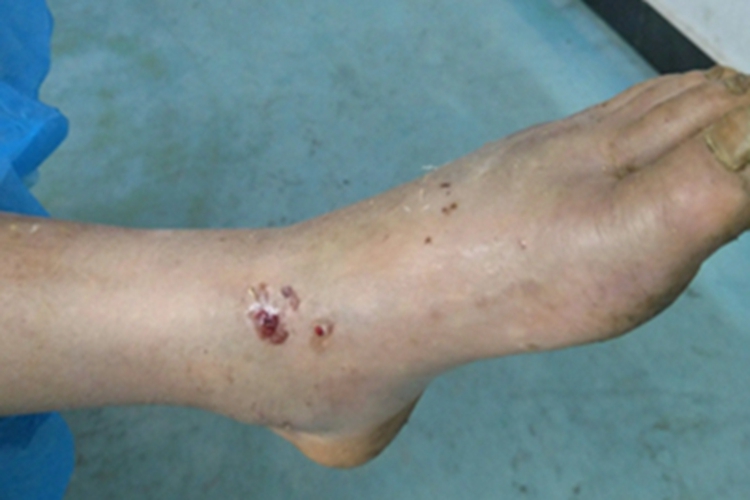

蛇咬伤较为严重的患者,在脚踝部位可留下一对较大而深的齿痕,类似于小孔,同时还伴有局部肿胀、血疱等症状,血疱主要发生于齿痕处,颜色为鲜红或暗红。